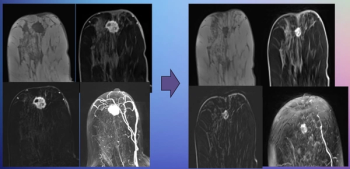

New research presented at the Society for Breast Imaging (SBI) conference suggests that abbreviated MRI is comparable to full MRI in assessing pathologic complete response to neoadjuvant chemotherapy for breast cancer.